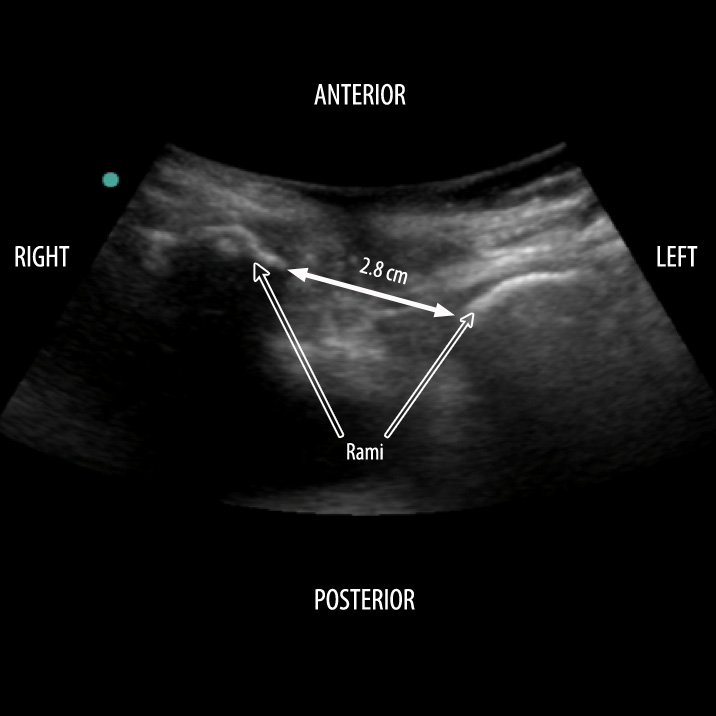

Time to reshare the SECONDS checklist of interpreting kidney #POCUS 👇

✅S - Size

✅E - (cortical) Echogenicity

✅C - Collecting system (hydro)

✅O - Outline (masses)

✅N - Notable lesions

✅D - Doppler

✅S - Surroundings (perinephric pathology)

#Nephpearls #MedEd #FOAMed